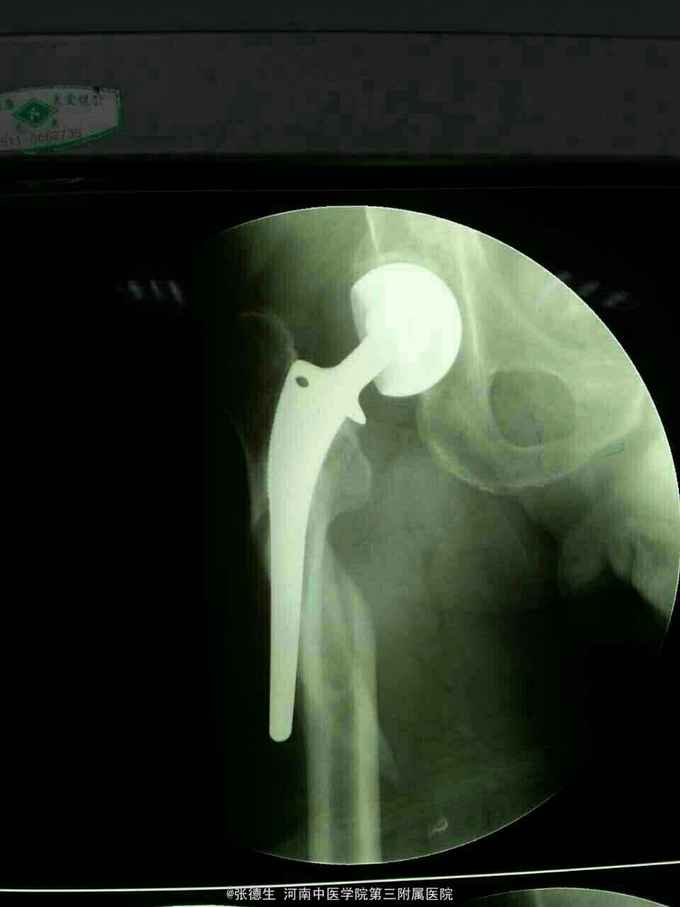

外伤后右髋部疼痛1天 患者男,77岁,五年前曾因股骨颈骨折行右股骨头置换术,1天前不慎摔倒,致右髋部疼痛,急来院,门诊拍片示右股骨假体周围骨折。

右髋部肿胀疼痛,异常活动,触及骨擦感,